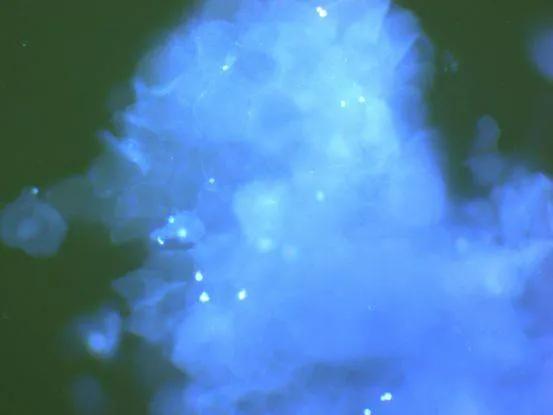

图为显微镜下的马拉色真菌

图为伍德灯下的猫藓呈荧光反应